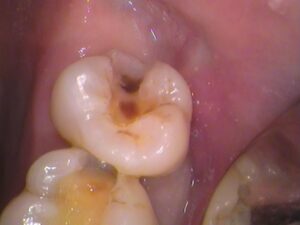

7番目の歯の詰め物を削っていくと、

中から茶色い虫歯が出てきました。

茶色い虫歯が内部で広がっています(*_*)

6番目の歯から見てみると、

歯と歯の間から虫歯になっており、

表面から虫歯を削っていくと、

歯の間も黒く虫歯の侵入があるのが分かります。